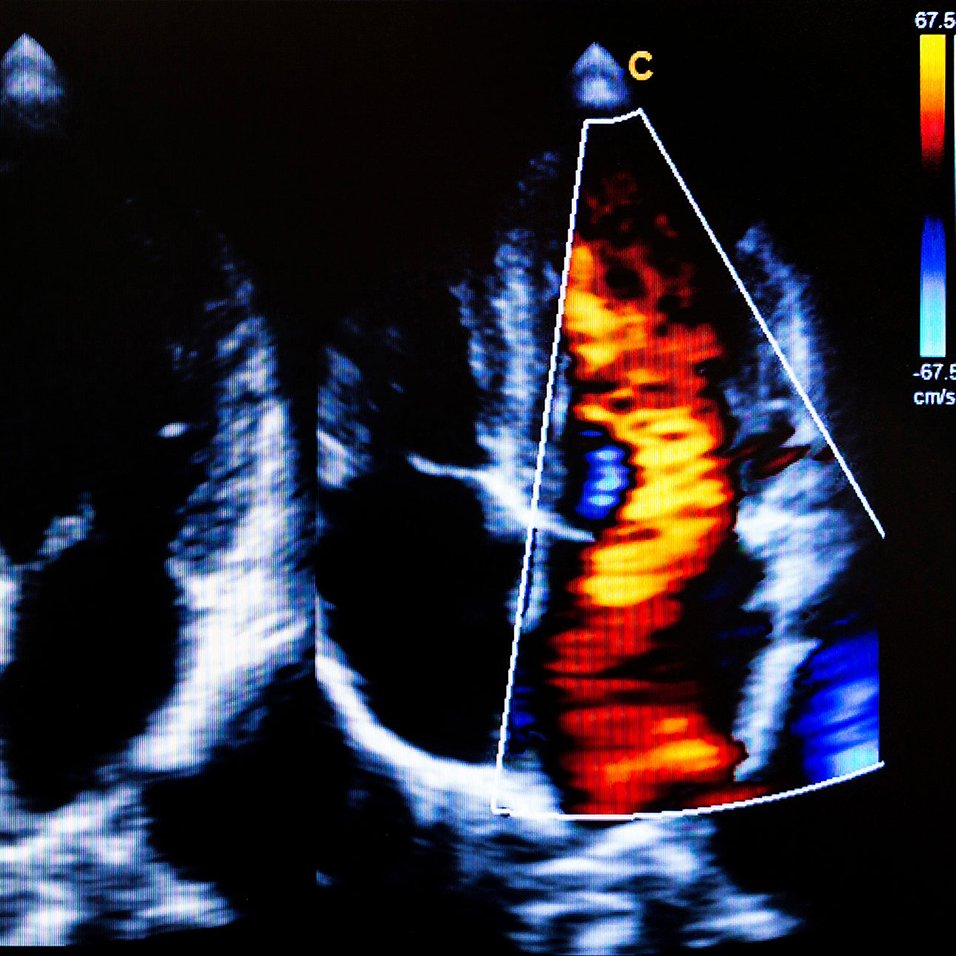

Congestie bij hartfalen beter behandeld

De 27ste Prijs Jacqueline Bernheim, ter waarde van € 30.000, maakt sinds kort deel uit van een reeks para-academische prijzen van de...